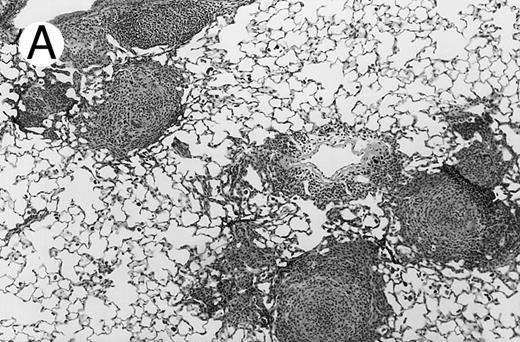

Three groups of X-CGD mice were studied: (1) control X-CGD mice; (2) X-CGD mice challenged 10 to 14 weeks after transplantation with MSCV-91Neo–transduced X-CGD BM; and (3) X-CGD mice challenged 5 to 8 weeks after transplantation with mixtures of wild-type and X-CGD BM cells. The results are summarized in Table 2. There were no deaths during the 17 to 21 days after challenge except for one mouse in the second group who died of complications of anesthesia on day 1. All 16 control X-CGD mice that were not transplanted developed lung disease after respiratory exposure to A fumigatus conidia. A common finding in lung tissue was the presence of multiple foci of granulomatous microabscesses that also contained occasional giant cells (Fig 3A). Rare hyphae were also seen. Larger inflammatory nodules containing numerous neutrophils and hyphae were seen in some mice (Fig 3B). Large abscesses with necrotic centers or regional bronchopneumonia were also occasionally observed (not shown). In 4 of 4 X-CGD mice transplanted with marrow transduced with the low-titer MSCV-h91Neo vector, who had only 1% to 2% NBT+ PB neutrophils at time of challenge, lung disease similar to that seen in untransplanted X-CGD mice was seen (Table 2). However, only minimal, if any, inflammatory changes were seen in 9 of 9 X-CGD mice with ≈50% to 80% NBT+ circulating neutrophils after transplantation with BM transduced with the high-titer vector (Table 2). Lungs appeared either normal (except for macrophages containing colloidal carbon that was administered along with conidia to mark the site of delivery) or contained occasional collections of mononuclear cells, typically in perivascular or peribronchial locations (Fig 3C). These findings were similar to those seen in lungs of wild-type mice after challenge with these numbers of A fumigatus conidia (unpublished observations, 1996).

Pulmonary findings 17 to 21 days after intratracheal instillation of A fumigatus conidia in X-CGD mice. Lung tissue was obtained 17 to 21 days after intratracheal challenge with 150 to 500 A fumigatus conidia, and stained with hematoxylin and eosin (A and C) or Grocott methamine silver (B). Representative photomicrographs obtained from three different mice are shown (original magnification × 100). (A) Untransplanted X-CGD mouse. Granulomatous microabscesses are seen, with occasional giant cells. (B) Untransplanted X-CGD mouse. Large inflammatory nodules with a central collection of neutrophils and numerous hyphae are seen. (C) X-CGD mouse transplanted with marrow transduced with the high-titer MSCV-m91Neo retrovirus. Occasional mononuclear cells in perivascular spaces and alveoli are seen, along with macrophages containing colloidal carbon (arrows) that was administered with the conidia to mark the site of delivery.